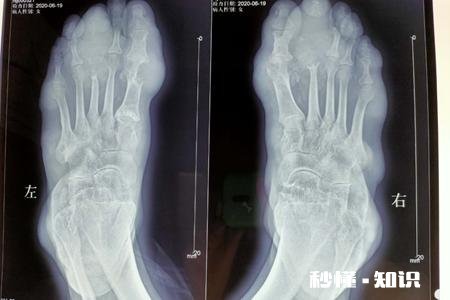

【痛风需要做哪几项检查】2、就是X线摄片检查,X线摄片检查是检查痛风的主要检查项目,急性痛风早期仅表现为软组织的肿胀、关节显影正常 , 随着病情的进展与痛风石邻近的骨质 , 可出现不规则或枫叶状的缺损,边缘呈鞘状突起,关节软骨缘破坏 , 关节面不规则;